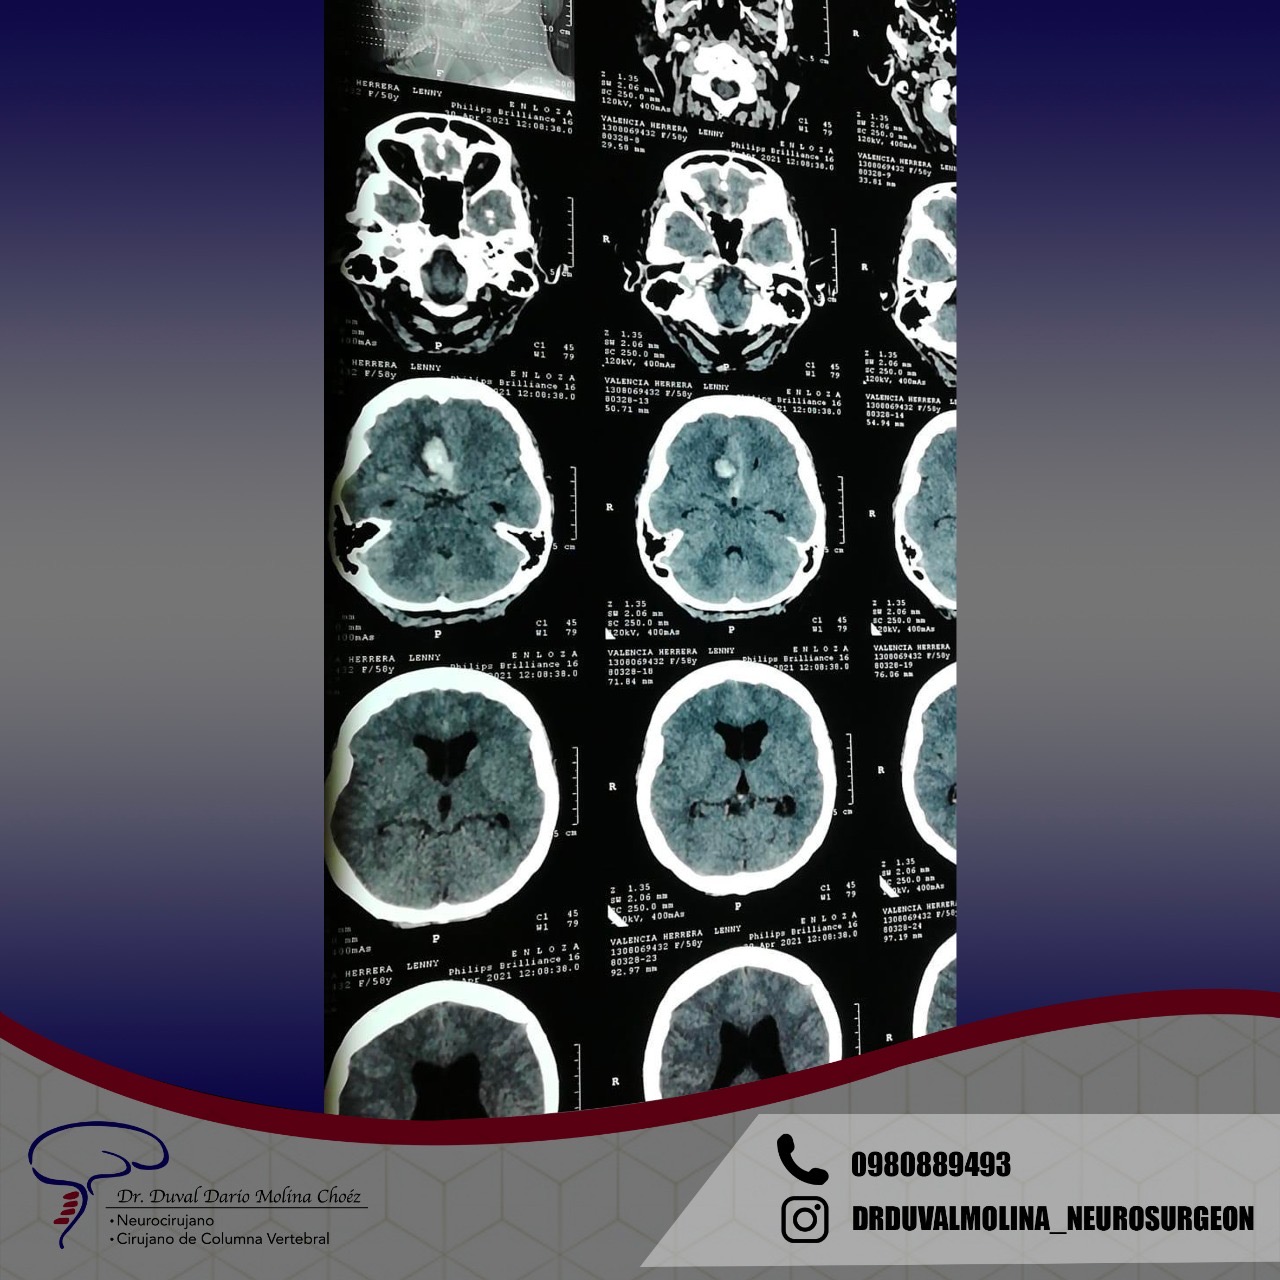

Los aneurismas son un abultamiento de una pared arterial que representa un punto débil. Se encuentran en alrededor del 2-3% de la población y suelen permanecer en silencio hasta que se rompen. Un aneurisma roto generalmente se presenta con el peor dolor de cabeza que haya existido y un inicio rápido de problemas neurológicos. El patrón característico de la hemorragia se denomina «hemorragia subaracnoidea».

También puede causar la muerte instantánea o provocar una discapacidad permanente. En algunos casos, hay un fuerte historial familiar o una condición genética. La afección hereditaria más común es la enfermedad renal poliquística del adulto. Los factores de riesgo para la ruptura del aneurisma incluyen el tabaquismo, la hipertensión mal controlada y el esfuerzo excesivo. Si no se trata, existe un riesgo anual acumulativo de ruptura y se recomienda una vigilancia periódica.

El patrón de hemorragia típico que se observa después de la ruptura de un aneurisma. La forma y la ubicación del aneurisma pueden predecir su comportamiento y también determinar qué opción de tratamiento es probable que sea la mejor. Alternativamente, si el aneurisma representa un bajo riesgo de ruptura o un alto riesgo quirúrgico, podemos optar por seguirlo con imágenes en serie. La intervención está diseñada para detener el flujo de sangre hacia el aneurisma, eliminando así el riesgo de hemorragia. Se puede realizar de forma endovascular rellenando el aneurisma desde dentro («coiling» endovascular), o mediante técnicas microquirúrgicas abiertas («clipaje»).